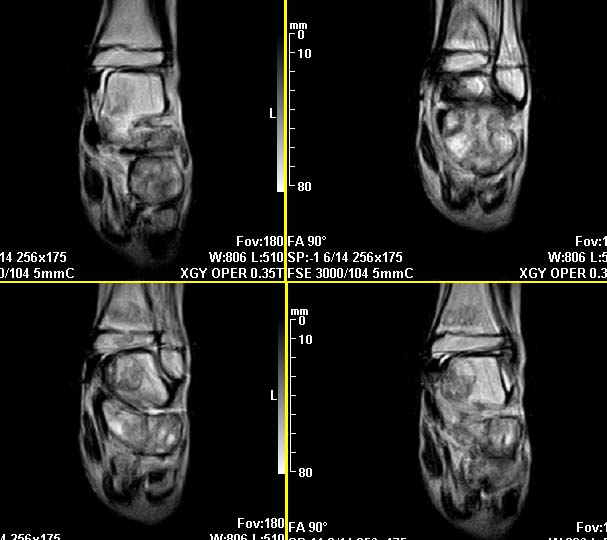

m,9y,左足肿痛半年,无皮肤发红,诱因为外伤后起因。无发烧,无其他疾病。临床考虑多发血管瘤。mri增强后有强化,请分析。是骨髓瘤吗?

左足多发囊状膨胀性骨质破坏,边较清,关节间隙及软组织未见明显异常。结合临床。可排除炎症性病变。病变中心为骨髓腔。有强化。中心坏死。嗜酸性肉芽肿可能大。

多发内生性软骨瘤

结合临床考虑血管瘤侵犯左足骨质。

今天从天津肿瘤医院传来消息:病理结果是非骨化性纤维瘤。